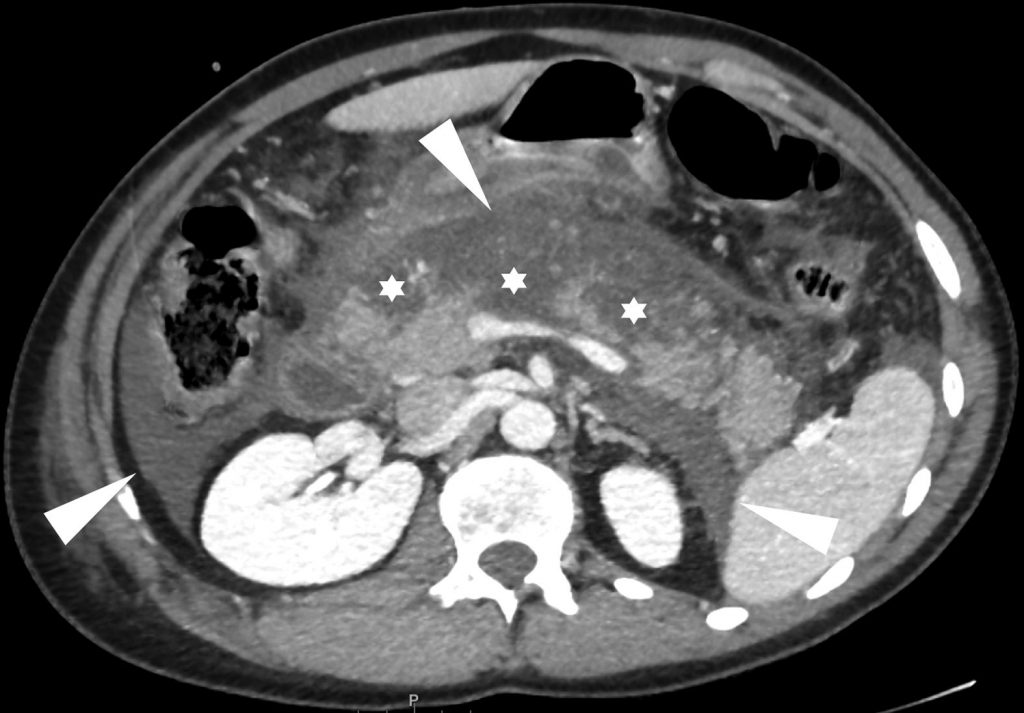

Fig. 11.2. Patient de 48 ans adressé pour douleur épigastrique aiguë.

La biologie permet le diagnostic de pancréatite aiguë. Coupes scanner de l’abdomen avec injection de produit de contraste iodé. Défaut de rehaussement de la glande pancréatique touchant 30 à 50 % de la glande et atteignant l’isthme, le corps et la queue, (4 points) (étoiles) et multiples collections liquidiennes (têtes de flèche) (4 points). Pancréatite aiguë grave (CTSI à 8).

Source : CERF, CNEBMN, 2022.